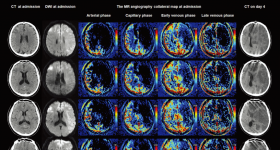

側(cè)支循環(huán)能夠決定組織的命運并影響急性缺血性中風的治療結(jié)果。其中,使用最佳成像方案中采用精確的側(cè)支估計方...